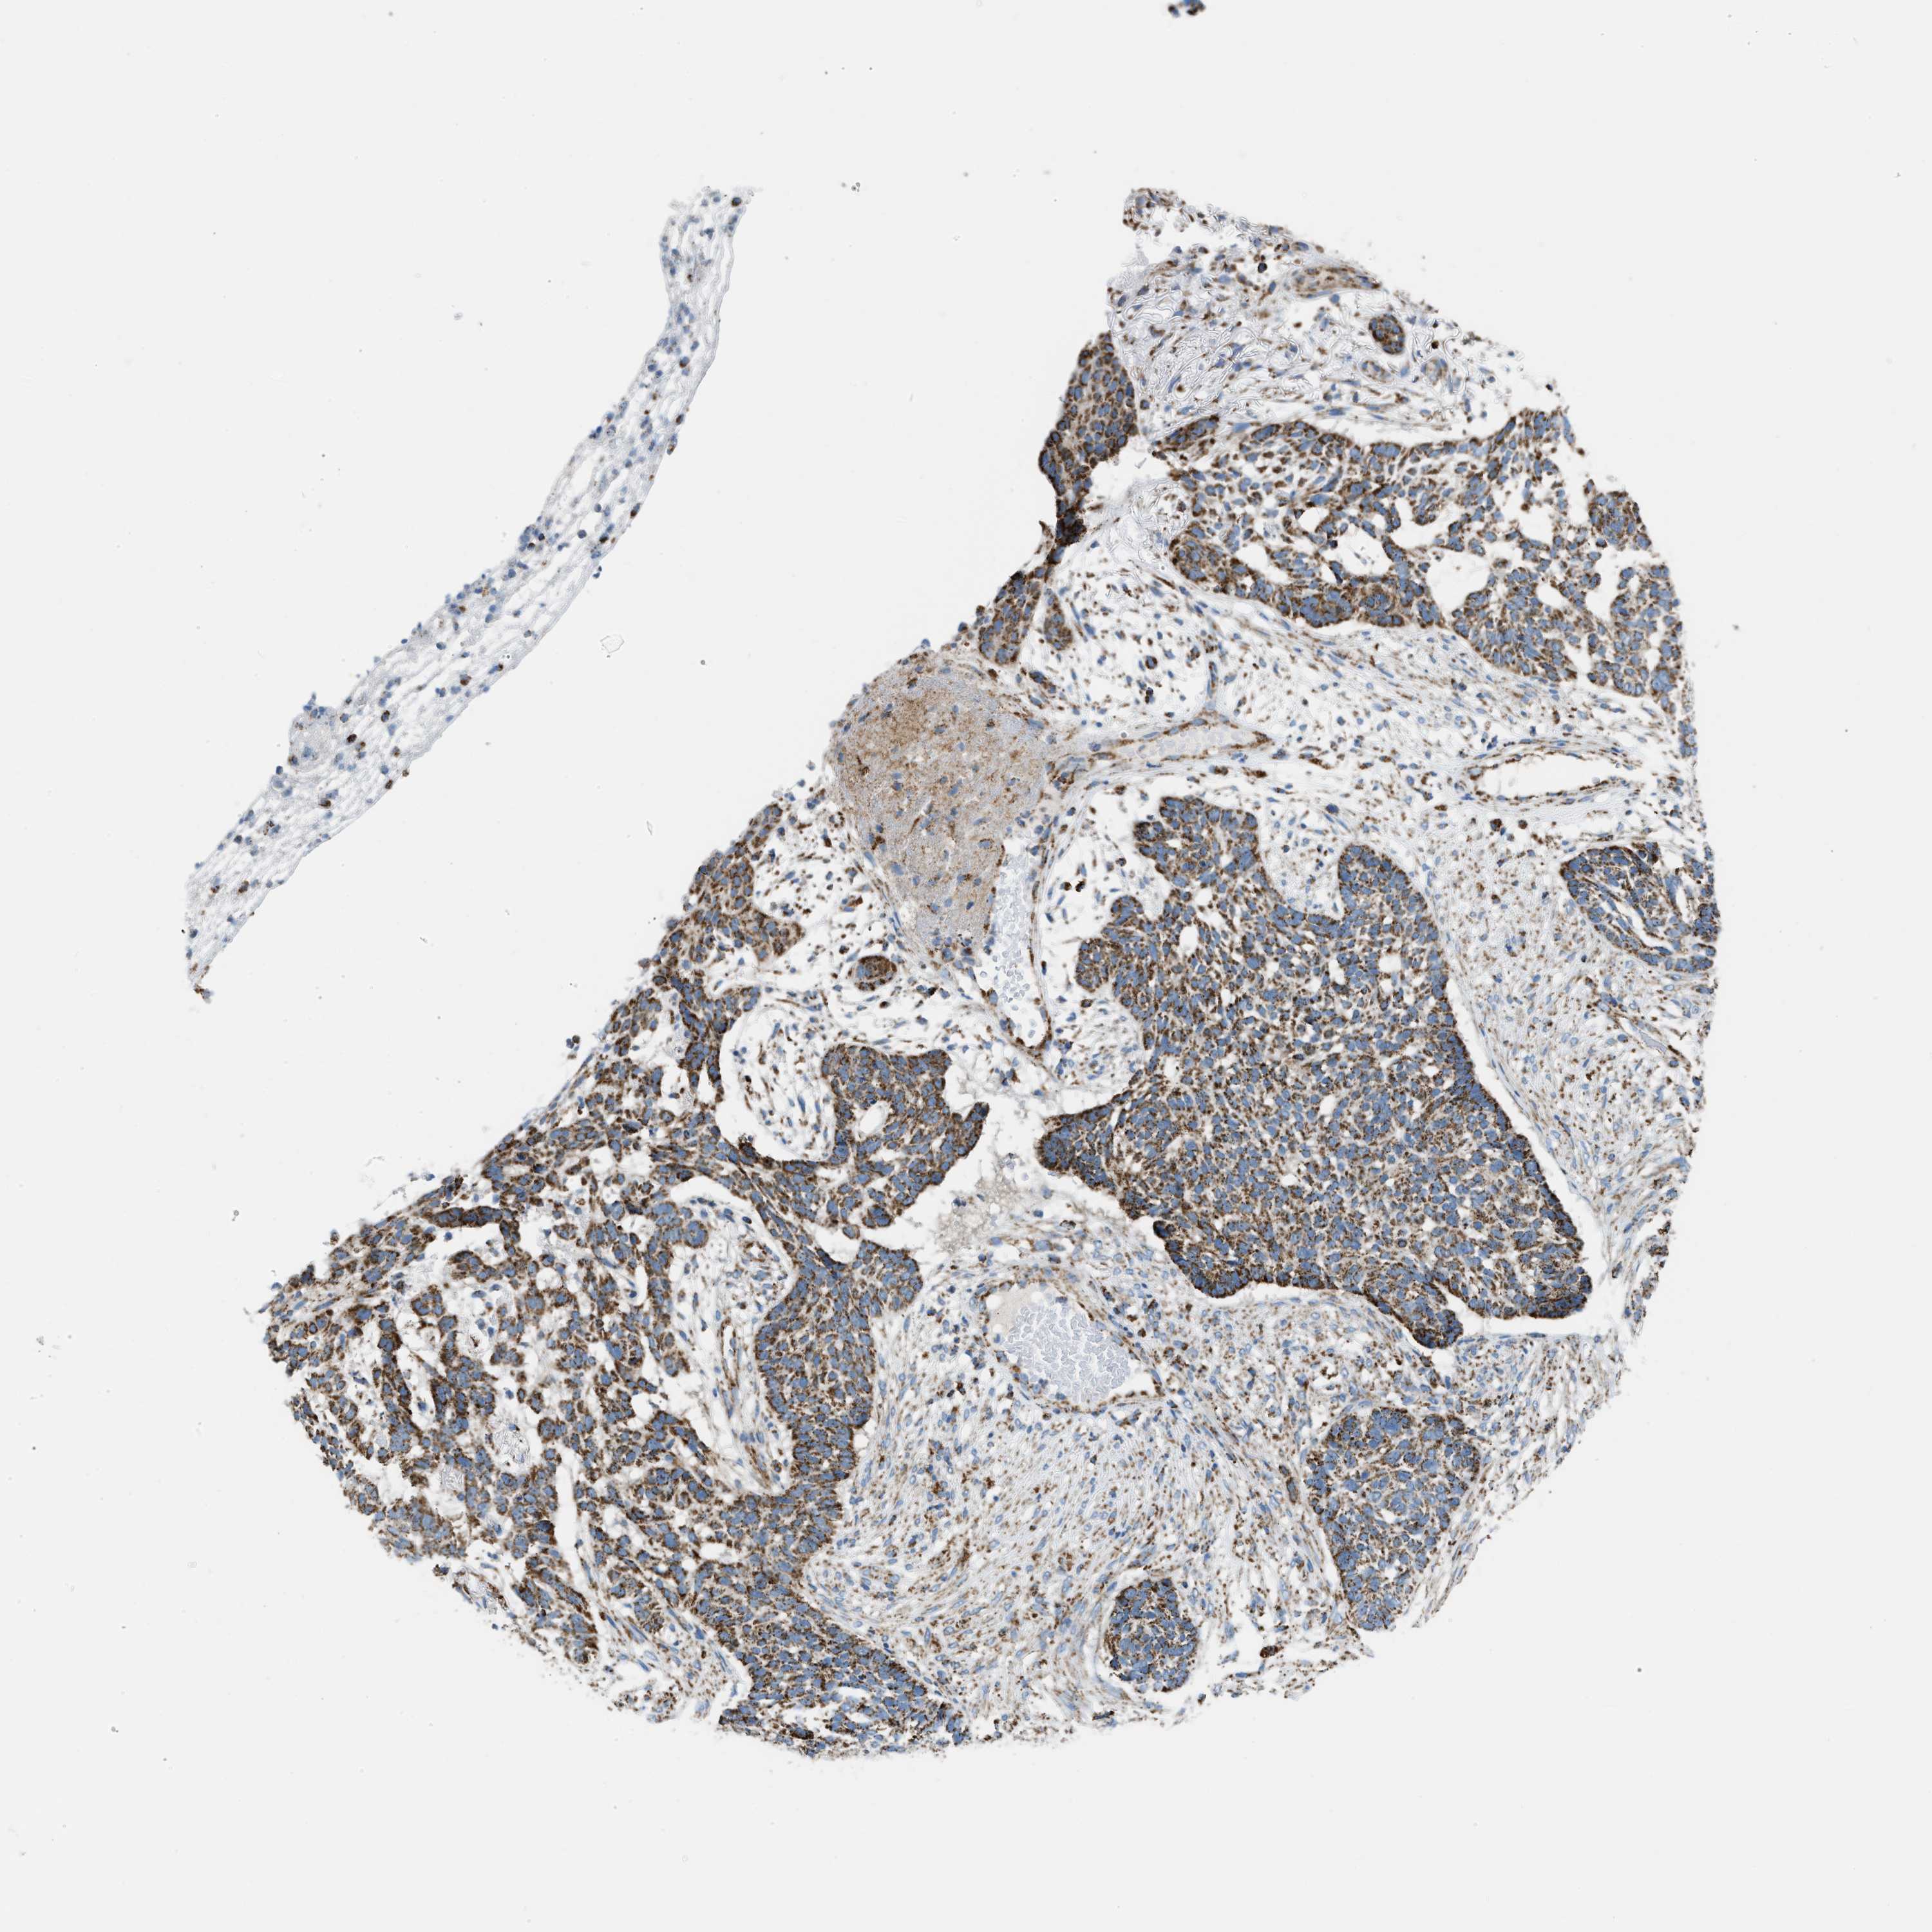

SKIN CANCER - Protein expressioni

A mouse-over function shows sample information and annotation data. Click on an image to view it in a full screen mode. Samples can be filtered based on level of antibody staining by selecting one or several of the following categories: high, medium, low and not detected. The assay and annotation is described here.

Each image is clickable and will lead to virtual microscopy that enables deeper exploration of all samples and also displays staining intensity scores, fraction scores and subcellular localization as well as patient and tissue information for each sample.

Antibody HPA018910

Squamous cell carcinoma, NOS